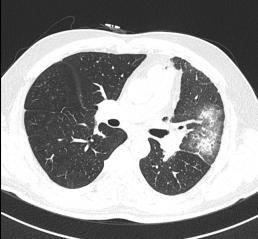

2020年5月14日行胸部CT:

1.左肺上叶炎症;

2.右肺上叶尖段慢性炎症;

3.两肺上叶、左肺下叶局限性肺气肿;

2020年5月24日复查胸部CT:

左肺上叶炎症,较前进展;

右肺上叶间质性病变,考虑间质性肺水肿;

右肺上叶尖段慢性炎症。

▎肺部增强CT(图片如下)

2.右上肺尖段少许慢性炎症;

3.纵隔多发肿大淋巴结,拟反应性增生,建议随诊;

4.拟左上肺多发体-肺动脉分流形成;

5.支气管动脉重建示左侧支气管动脉稍增粗。

反复阅读肺部CT并与影像科同事联系,患者肺部CT提示间质水肿、左肺上静脉显示不清,结合患者存在射频消融史,需要考虑肺静脉狭窄引起的咯血。

其中肺静脉增强CT检查及血管三维重建诊断PSV效果明显,该例患者我院首先完善了肺部动脉增强CT,影像科医生在报告中未报左肺静脉异常,我们反复阅读片子发现左肺静脉异常,从而进一步行右心导管、左心导管、肺动脉造影术,以此明确诊断;而使用心脏彩超诊断PVS中需警惕因操作者主观因素导致的诊断遗漏,注意加强与辅助科室之间的提醒。